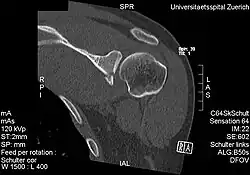

CT scan showing a bony Bankart lesion at the antero-inferior glenoid -